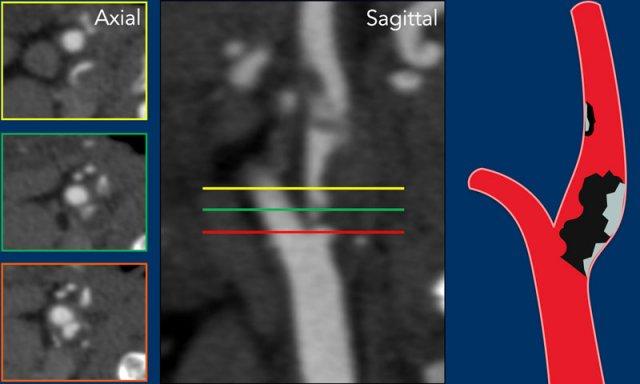

Gần tắc hoàn toàn

Trong trường hợp hẹp nặng hoặc gần tắc hoàn toàn, đường kính của ACI ở đoạn trên vị trí hẹp bị thu nhỏ và nhỏ hơn so với ICA bên đối diện cũng như ECA cùng bên.

Gần tắc hoàn toàn (2)

Trong trường hợp này, động mạch cảnh chung có đường kính bình thường (hình 1).

Có hẹp nặng với mảng xơ vữa vôi hóa một phần tại vị trí xoang cảnh (2).

ICA ở đoạn trên vị trí hẹp có khẩu kính nhỏ (3). Xem thêm mũi tên trên ảnh tái tạo mặt phẳng đứng dọc.

Các tiêu chí chẩn đoán gần tắc hoàn toàn bao gồm:

- Khẩu kính ICA đoạn xa nhỏ hơn so với ICA bên đối diện (hình 3).

- Khẩu kính ICA đoạn xa nhỏ hơn so với động mạch cảnh ngoài (ECA) cùng bên (hình 3).

Vận tốc đỉnh tâm thu trên siêu âm Doppler thường tăng tương ứng với mức độ hẹp, tuy nhiên trong trường hợp gần tắc hoàn toàn, vận tốc đỉnh tâm thu sẽ giảm xuống mức rất thấp như trong trường hợp này (20 cm/giây).

Lưu ý mảng vôi hóa tại vị trí xoang cảnh và khẩu kính nhỏ của ICA đoạn xa, nhỏ hơn so với khẩu kính của ECA.